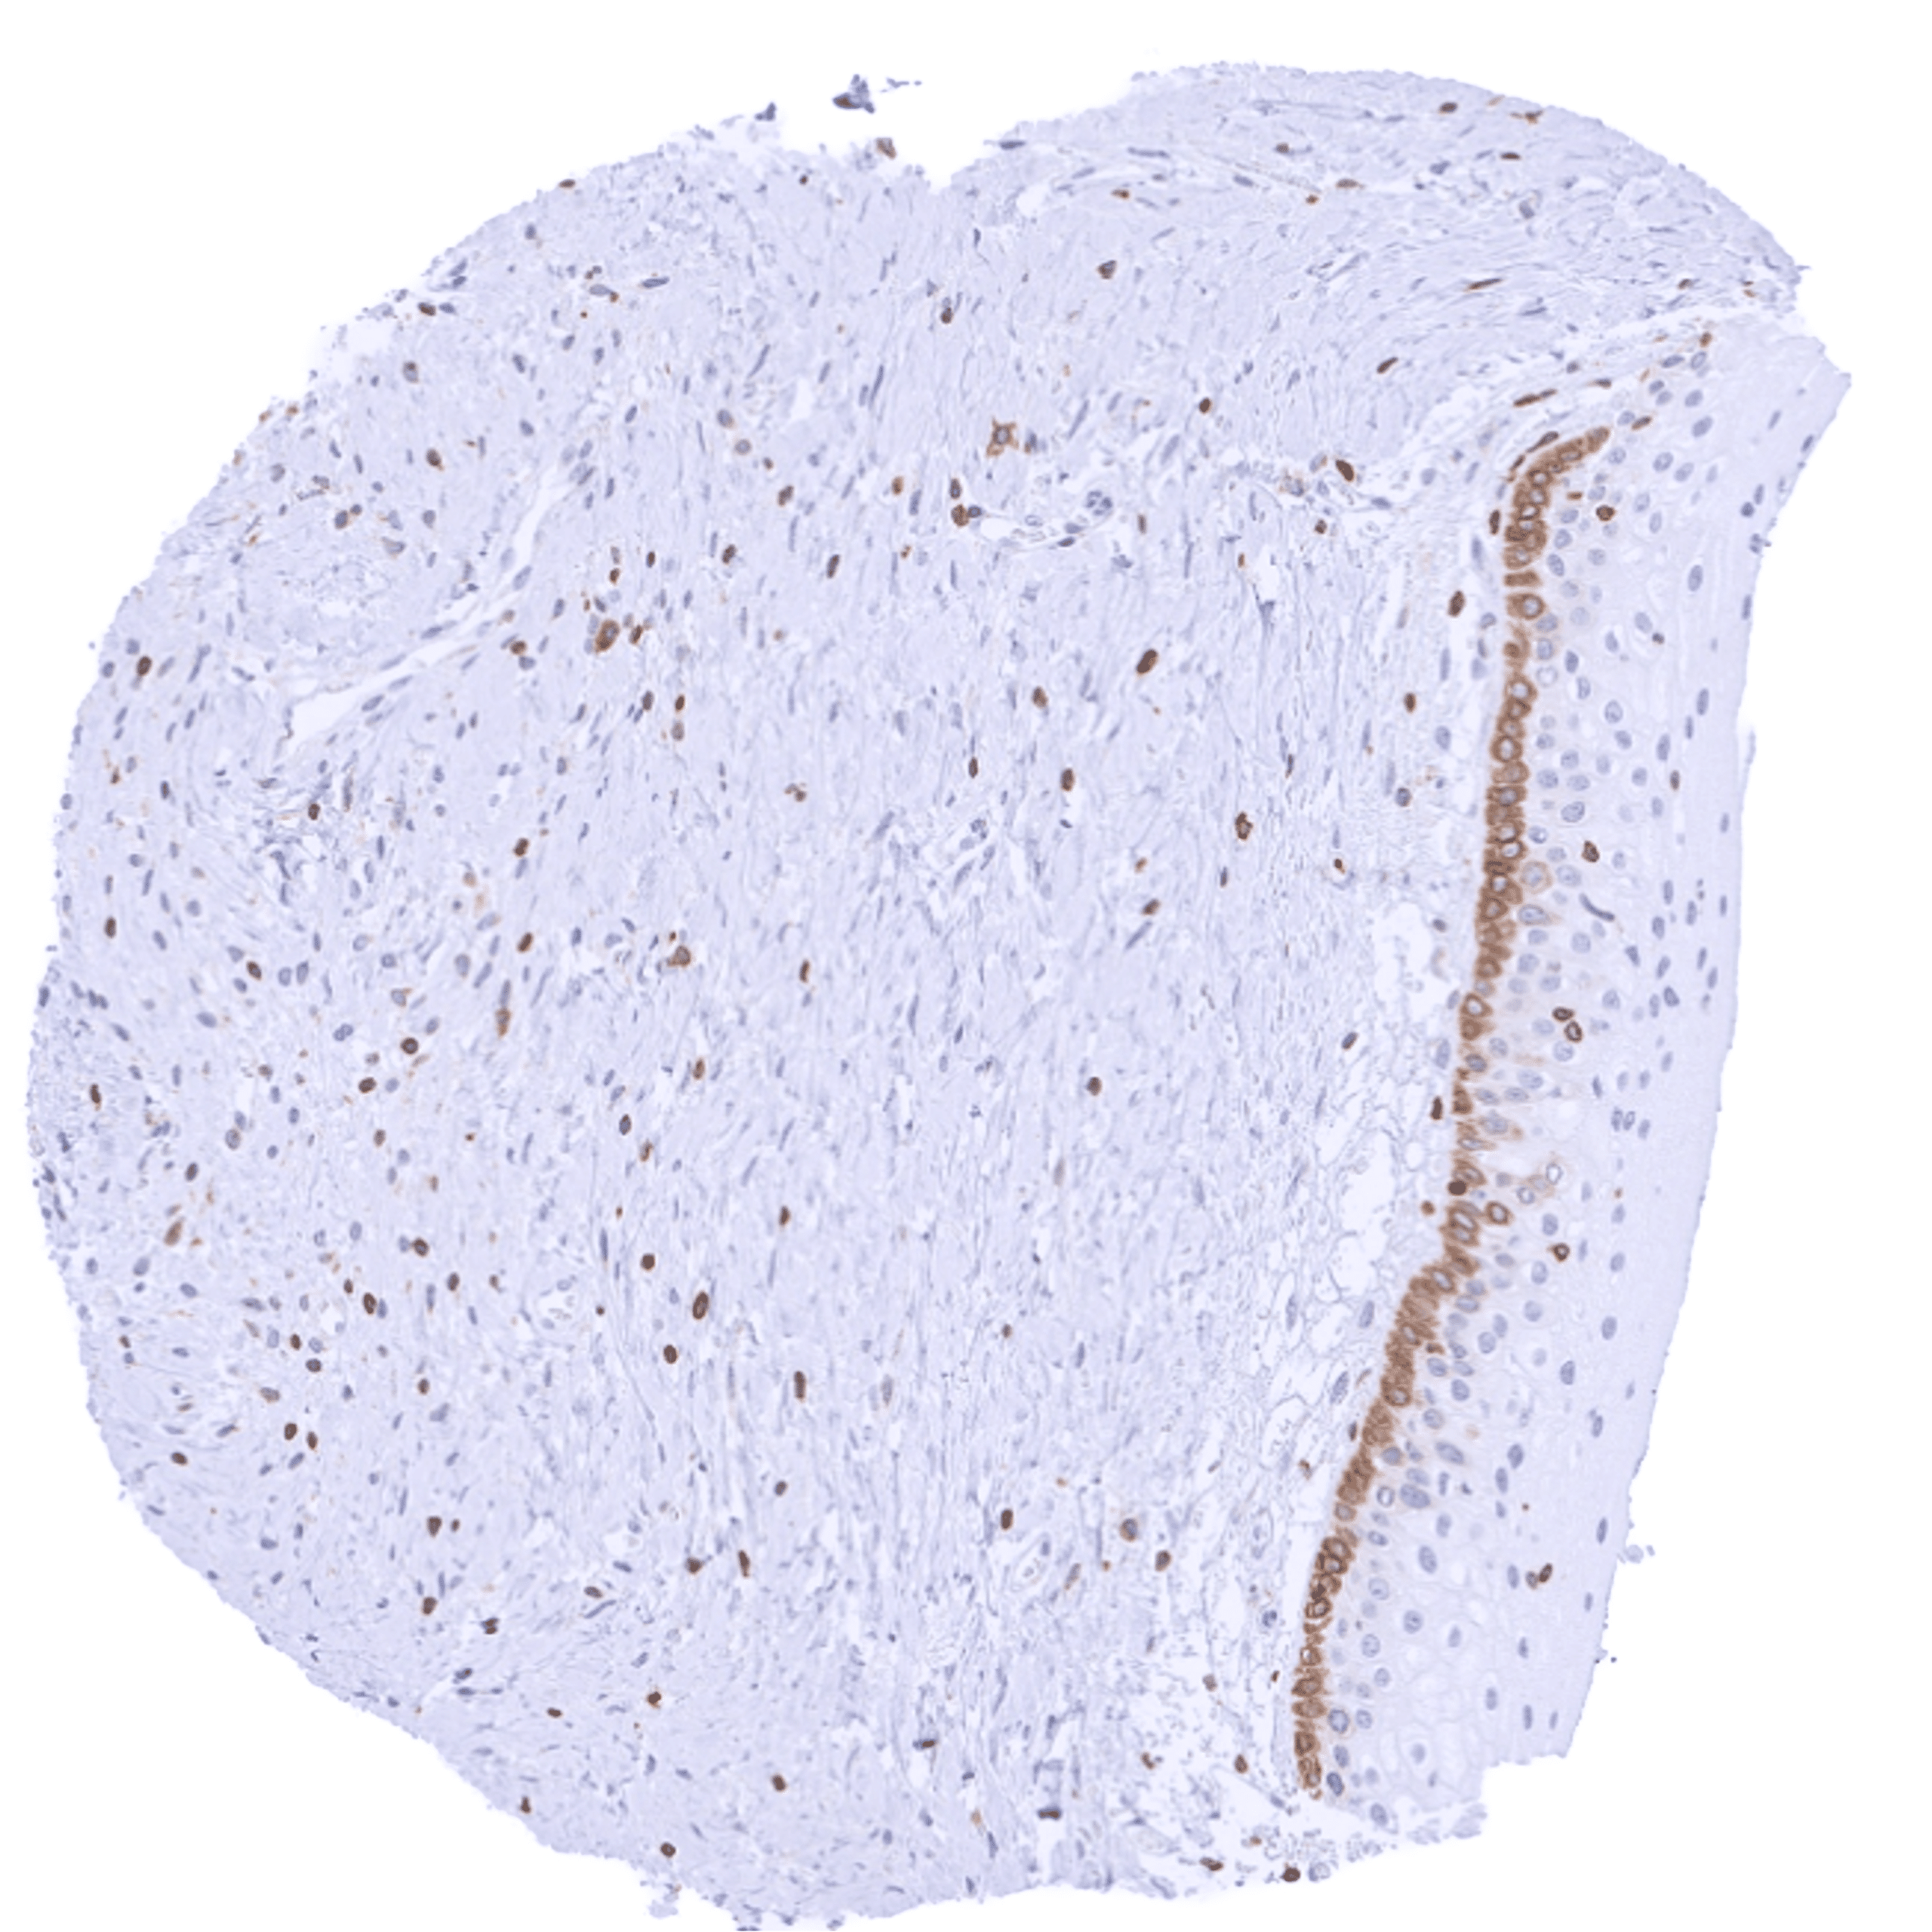

Positive control = Tonsil: A strong cytoplasmic bcl-2 staining should be seen in most interfollicular lymphocytes while most germinal centre cells are bcl-2 negative.

Negative control = Tonsil: The vast majority of lymphocytic cells from germinal centres must be bcl-2 negative while interfollicular lymphocytes are mostly positive.

| Tonsil | Strong bcl-2 positivity of a large fraction of lymphocytic cells in the interfollicular area and around germinal centres while almost all cells in germinal centres are bcl-2 negative. Squamous epithelium is bcl-2 negative although the basal cell layer may show weak positivity. | |